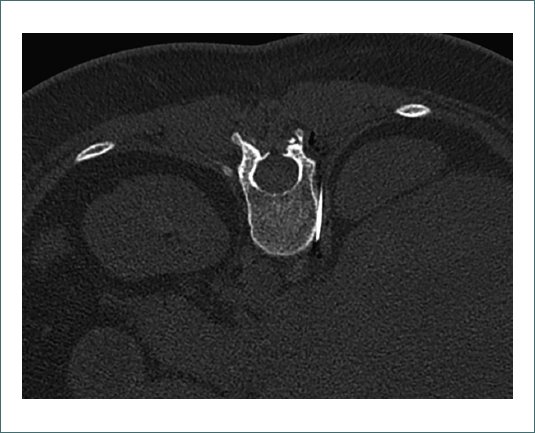

Dado el mal control analgésico y los elevados requerimientos de opioides, se opta por el abordaje de nervios esplácnicos (Fig. 3) derechos guiados por tomografía axial computerizada (TAC) (Fig. 4) mediante acceso retrocrural en decúbito prono. Se lleva a cabo bajo sedación endovenosa colaborativa y anestesia local en el punto de punción. Estimulación sensitiva positiva a 0,7 V (sensación dolorosa en epigastrio) y estimulación motora negativa hasta 2,5 V radiofrecuencia pulsada (RFP) 4 min, 42º, 45 V, 20 pps. Al finalizar la RFP se administra ropivacaína 0,5% más acetato de triamcinolona 20 mg.

Figura 4. Imagen de TAC de abdomen, plano axial. Abordaje transcrural derecho en decúbito prono.

Existen diversos abordajes para la realización del bloqueo esplácnico. Los más empleados en la actualidad son el abordaje transdiscal, que atraviesa el disco intervertebral T12-L1 y conlleva riesgo de discitis y dificultades técnicas en casos de degeneración, y el abordaje retrocrural. Los abordajes anteriores han caído en desuso debido al riesgo de perforación visceral, lo que hace imprescindible la profilaxis antibiótica en estos casos. En este paciente, se empleó el abordaje retrocrural, el cual se observa en la figura 3 (esquema anatómico) y en la figura 4 (imagen de TAC). La técnica consistió en colocar al paciente en decúbito prono, identificar los cuerpos vertebrales de T11 y T12, y avanzar las agujas hasta el tercio anterior de estos para alcanzar los nervios esplácnicos.

Diversos factores influyen en la efectividad del procedimiento, incluyendo la modalidad de imagen utilizada para su guía (fluoroscopia, TAC, ecografía o ecoendoscopia). En este caso, se optó por TAC debido a su capacidad para proporcionar una visión tridimensional, reduciendo el riesgo de complicaciones, y por su accesibilidad en nuestro centro. Además, el volumen, concentración y técnica de administración de los agentes neurolíticos o neuromoduladores también tienen impacto en la eficacia del bloqueo.